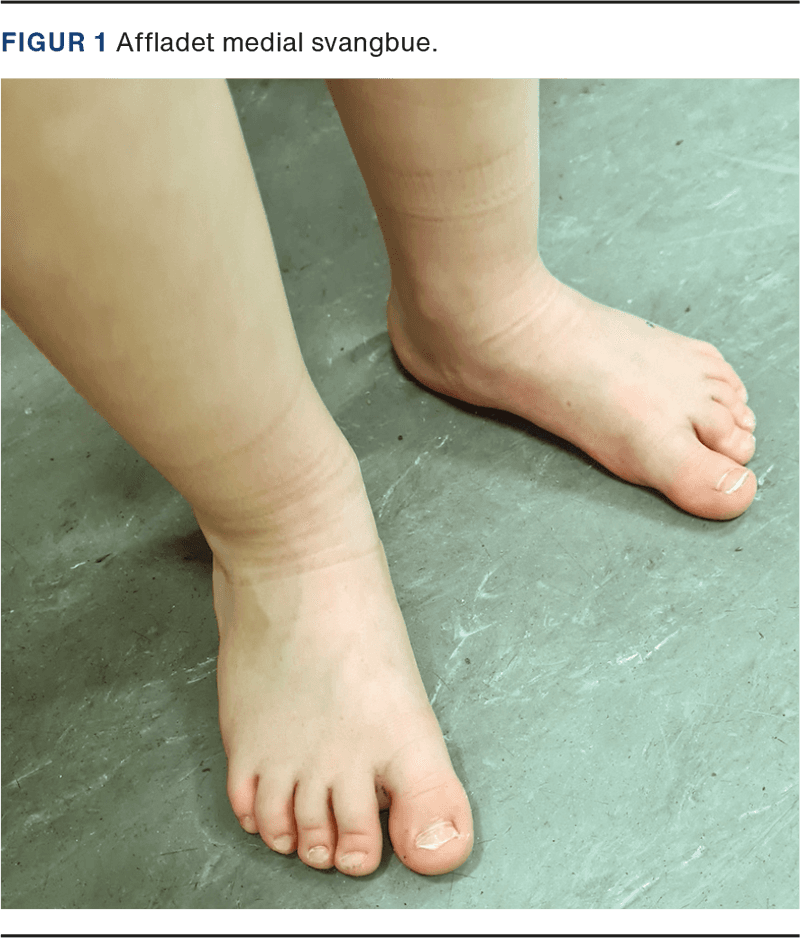

Diagnostik, evaluering og behandling platfødder børn | Ugeskriftet.dk

Diagnostik, evaluering og behandling platfødder børn | Ugeskriftet.dk

Diagnostik, evaluering og behandling platfødder børn | Ugeskriftet.dk

Diagnostik, evaluering og behandling platfødder børn | Ugeskriftet.dk